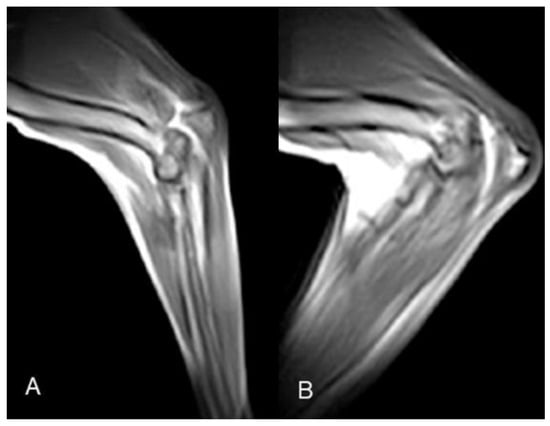

Figure 4. Case 6 elbow k-MRI sample images. (A) Neutral starting position; (B) point of maximum flexion.

Figure 5. Case 6 stifle k-MRI sample images. (A) Starting position, normal femorotibial alignment. (B) TCT endpoint, cranial subluxation of the tibia is visible, due to surgical cranial cruciate ligament resection; (C) flexion and (D) extension movement, femorotibial, no subluxation visible.

The evaluation of elbow kMRI studies was unacceptable in Case 5 (both sides), our first attempts at this region. The passive movement applied to the elbow was inadequate (too rapid and not fluid), causing artifacts and the variation of a constant mid-sagittal plane. The overall evaluation of Case 6 elbow kMRI study was good. The passive movement was improved, constantly fluid, and slower than the previous two attempts. Thus, artifacts decreased, image quality improved, and the mid-sagittal plane was overall retained. In all three post-surgical injury kMRI studies, articular instability was not evident during extension and flexion movements. The duration of the 2D HYCE S in Case 6, namely the time required for a single cycle of elbow flexion and extension, was 20–25 s (Figure 4, Supplementary Material Video S3).

3.3. Stifle kMRI

All stifle kMRI studies were evaluated as excellent. The passive movement, substantially improved after cervical and elbow kMRI studies, was constantly fluid and slow. Thus, artifacts decreased, and the mid-sagittal plane was overall retained. The duration of the 2D HYCE S, namely the time required for a single cycle of stifle flexion and extension, was 20–25 s. In all four post-surgical injury kMRI studies, articular instability was evident during TCT movements (Figure 5, Supplementary Material Video S4).